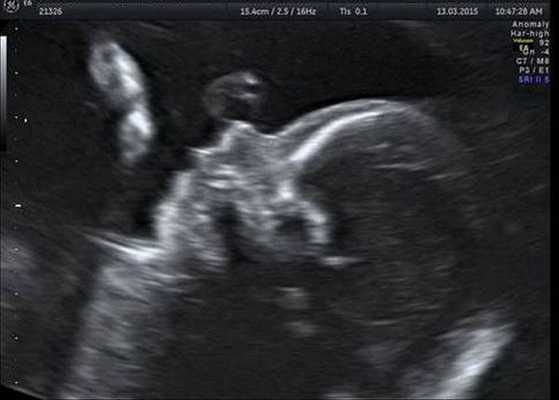

Вторичное небо развивается, как правило, до 12-й недели. Поэтому диагностику врожденных расщелин лица с помощью ультразвукового исследования (УЗИ) оптимально проводить на 11–12-й неделе беременности (именно тогда заканчивается формирование лица малыша).

Расщелина губы может быть диагностирована специалистом при правильном положении лица плода. Диагностика неба с помощью УЗИ сложнее. Однако опытный врач может зафиксировать нетипичное движение языка плода в боковой проекции. В ряде случаев специалисты не могут выявить этот дефект вплоть до самых родов, если ребенок закрывает личико ручкой или ножкой.

Как правило, патология формируется у плода в период внутриутробного развития. Поэтому заболевание можно выявить еще до родов, проведя ультразвуковое исследование. Расщелина появляется у зародыша в первые месяцы его развития, когда происходит формирование челюстно-лицевых органов. Кости в области твердого неба срастаются у плода к 11 неделе развития, к окончанию третьего месяца формируется мягкое небо. В целом образование неба происходит на 2-3 месяце внутриутробного развития. Нижняя губа формируется у плода в конце первого месяца, когда сращиваются нижнечелюстные отростки. Окончательное формирование верхней губы происходит в конце второго месяца, когда правый и левый верхнечелюстные отростки срастаются со срединным носовым отростком. Если в этот период отмечается негативное влияние эндогенных и экзогенных, а также генетически обусловленных факторов, этот процесс идет неправильно, и у малыша развиваются врожденные уродства лица – заячья губа и волчья пасть.

У малышей расщелина губы и неба диагностируется сразу после рождения, хотя при ультразвуковом исследовании плода расщелина губы определяется уже после 12 недели развития.

Диагностировать этот дефект у ребенка врач может еще на этапе внутриутробного развития, проведя ультразвуковое исследование.